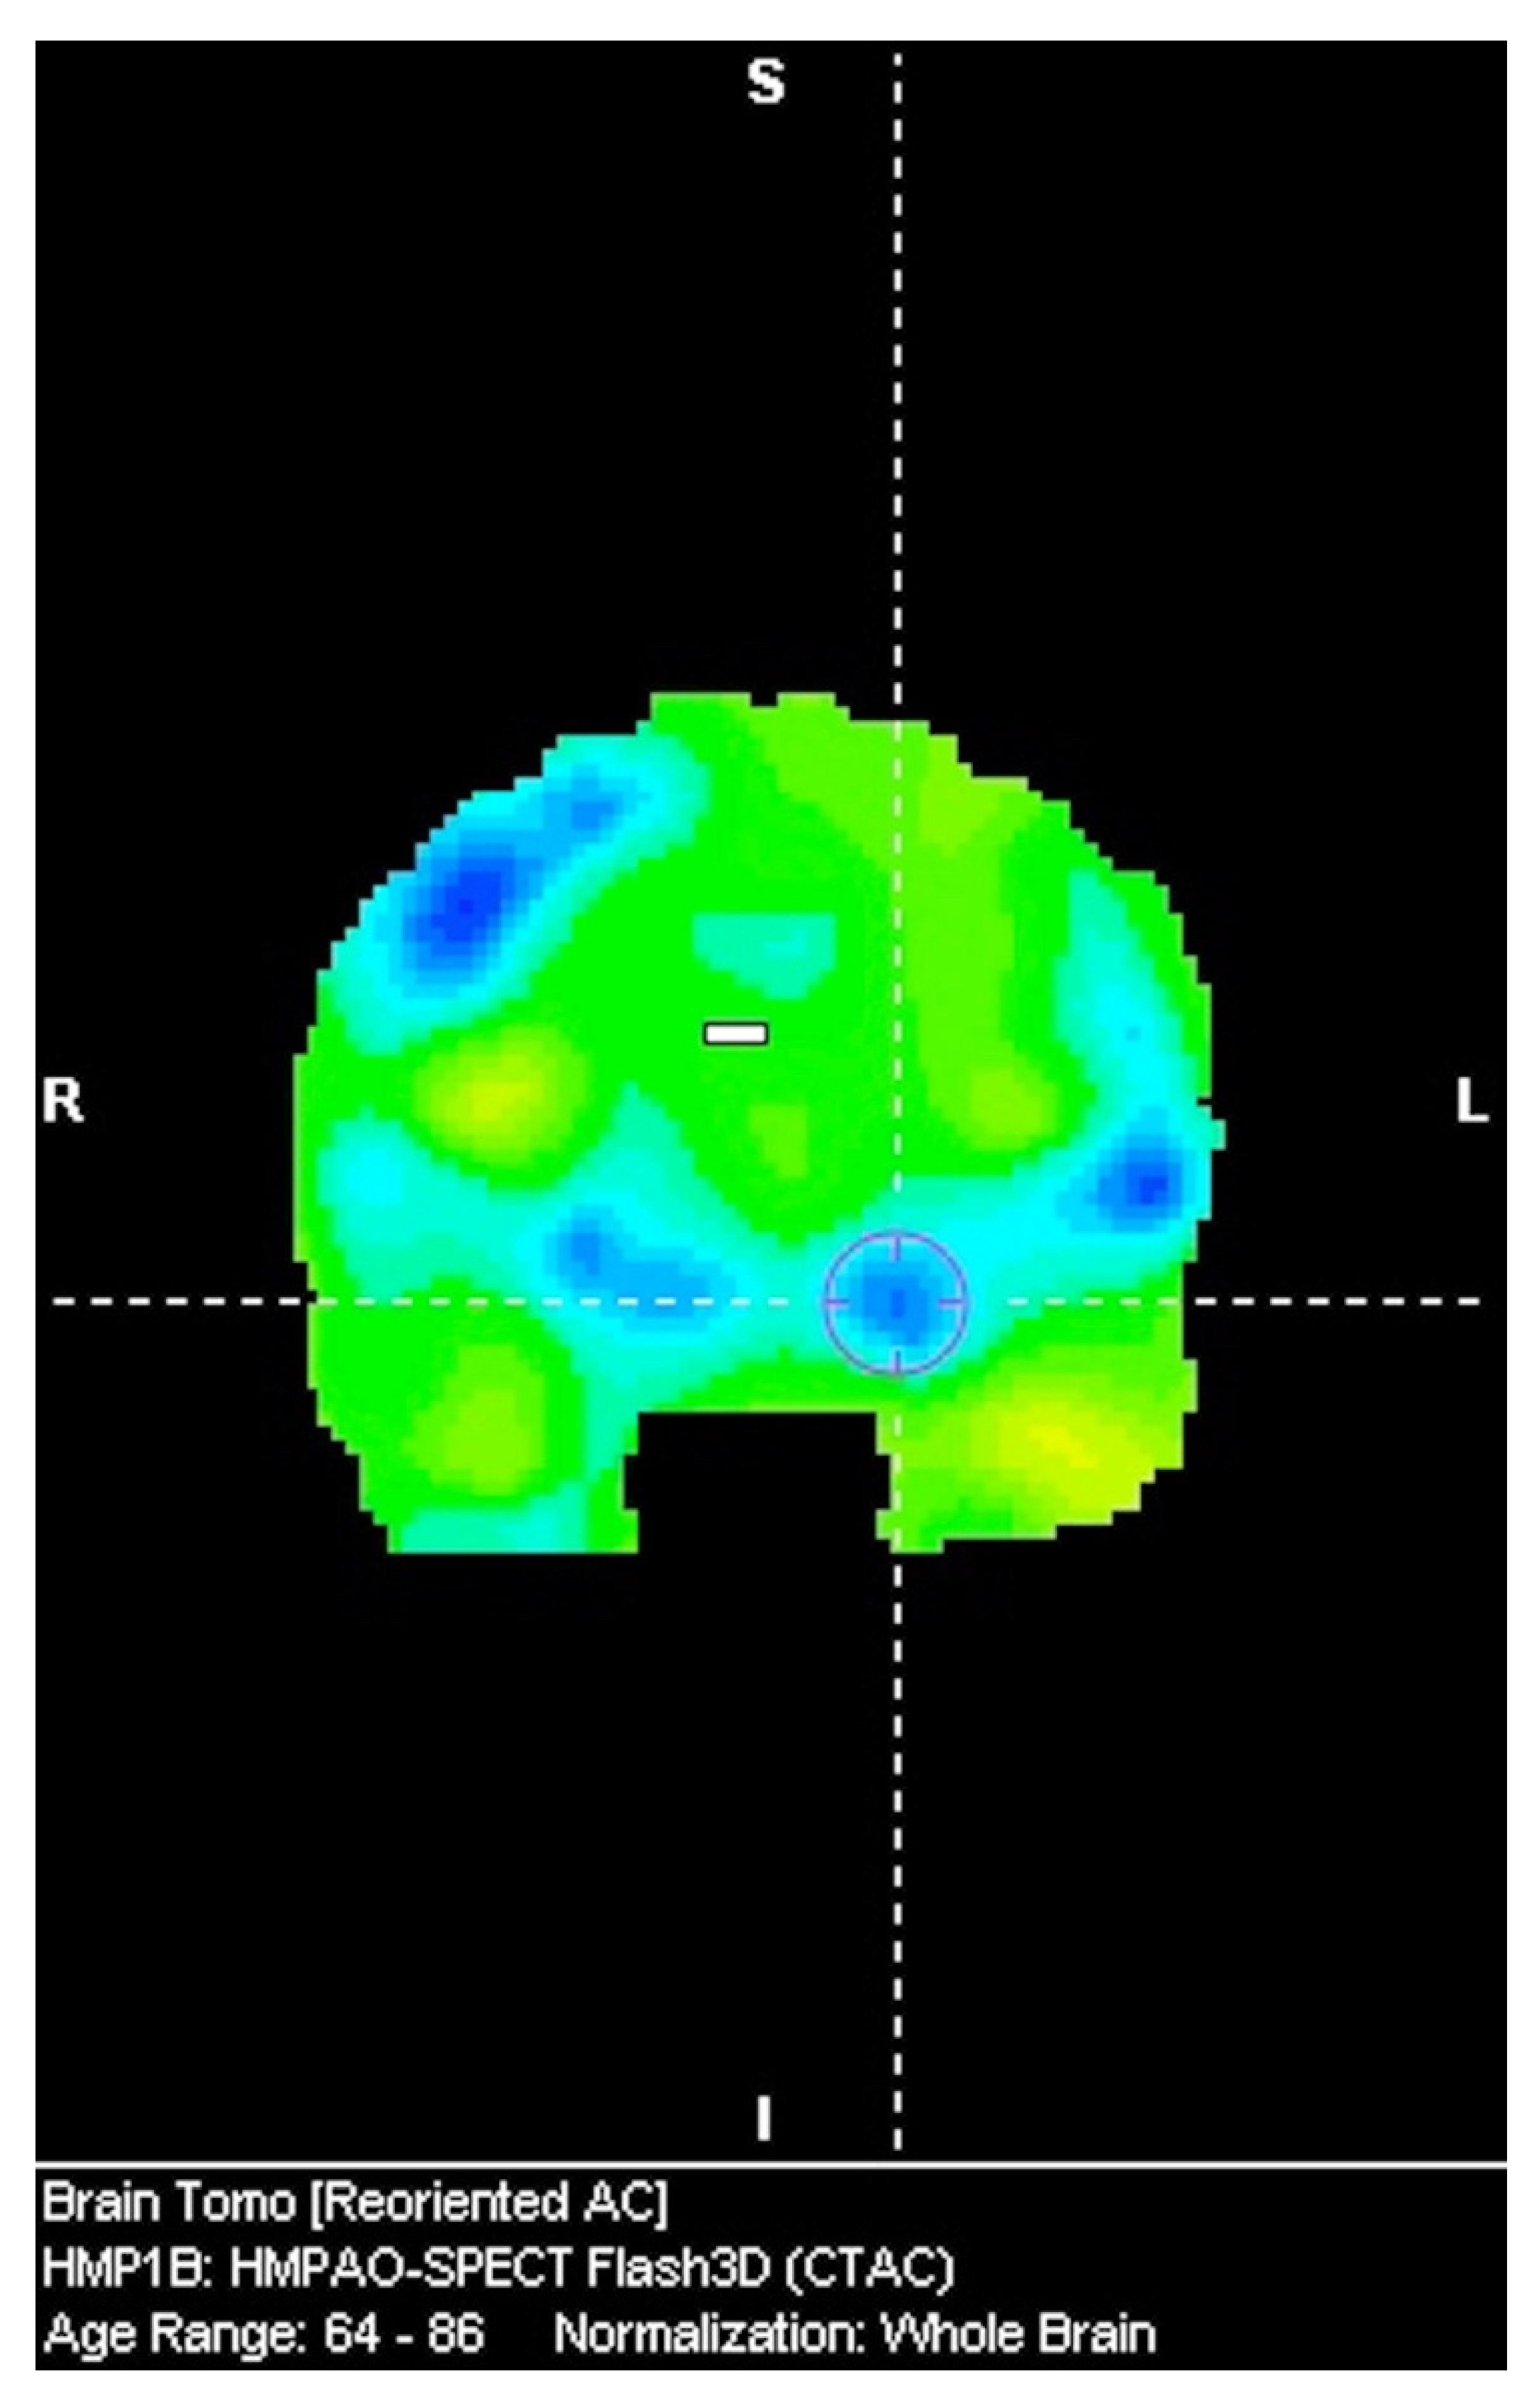

The Significance of Asymmetry in the Assessment of Brain Perfusion in Atypical Tauopathic Parkinsonian Syndromes

3.1. SPECT